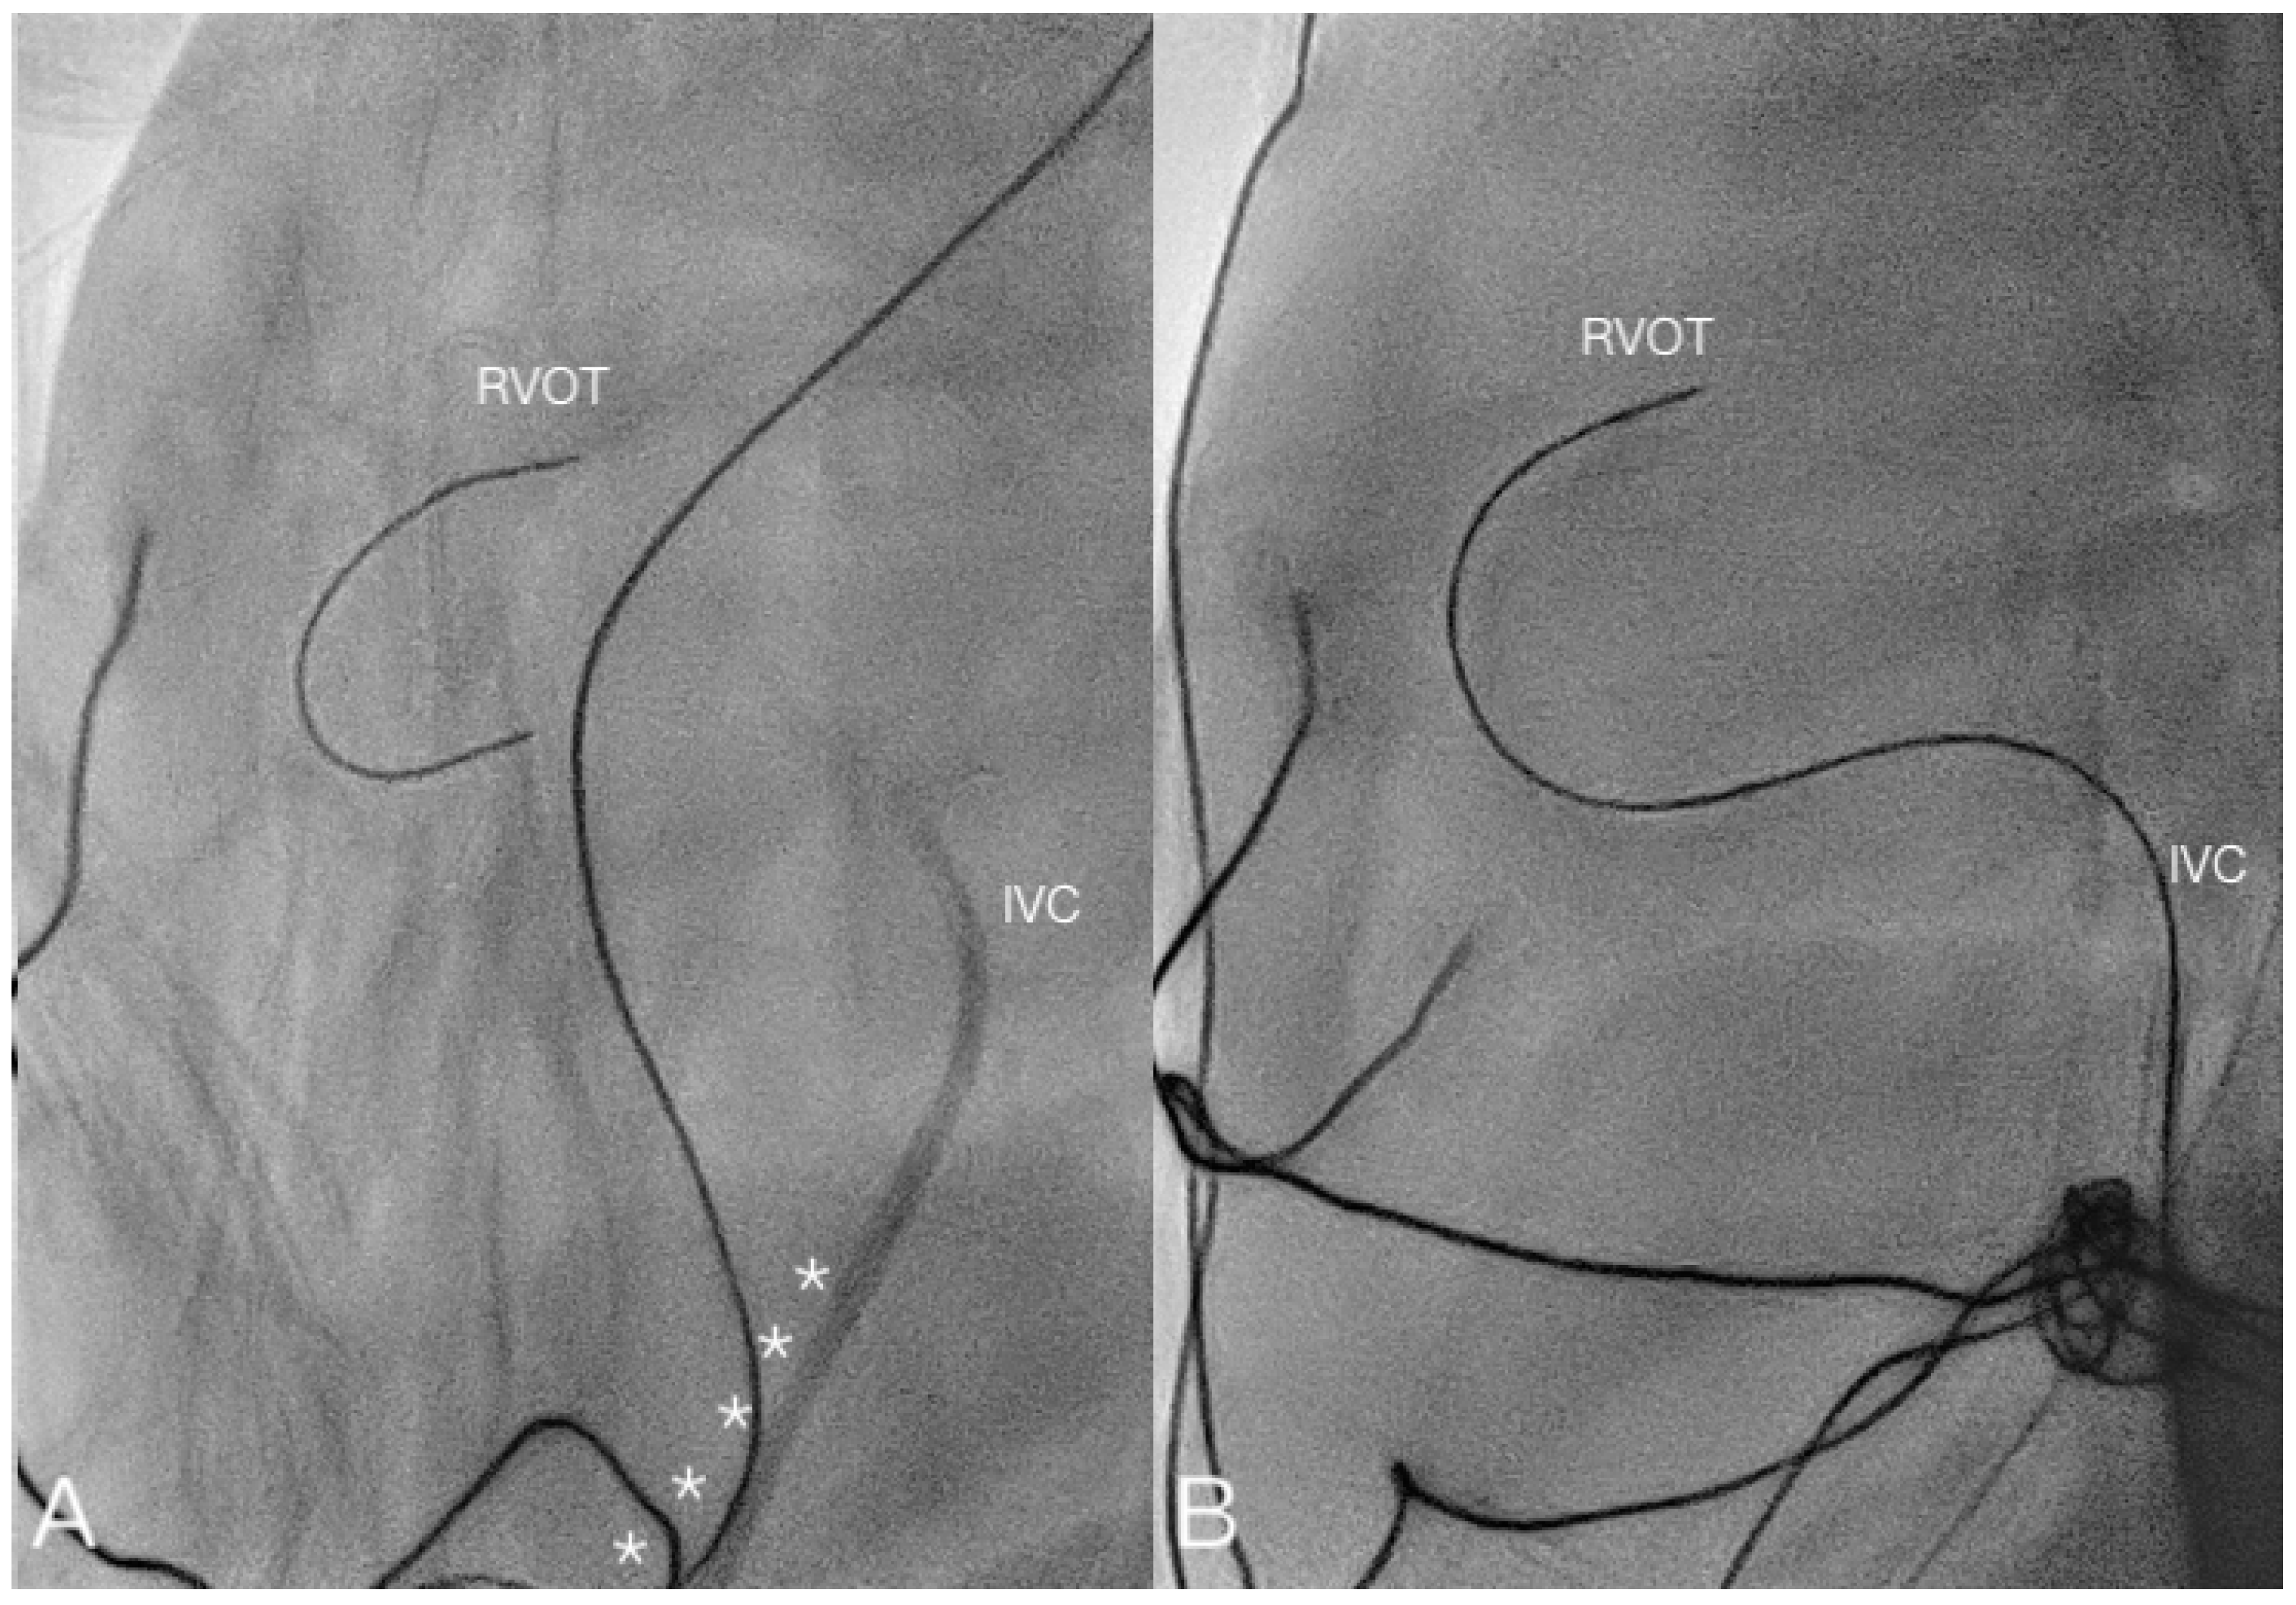

| 16 | 38 + 5 | 2692 | M | 5 | 2770 | PAIVS | 5 |

| 16 | 17 | PV perforation | 5 | Success | - | 50 m 18 s | 145 | PV perforation failure; femoral cannulation failure; shift to surgical pulmonary valvotomy and discharged |